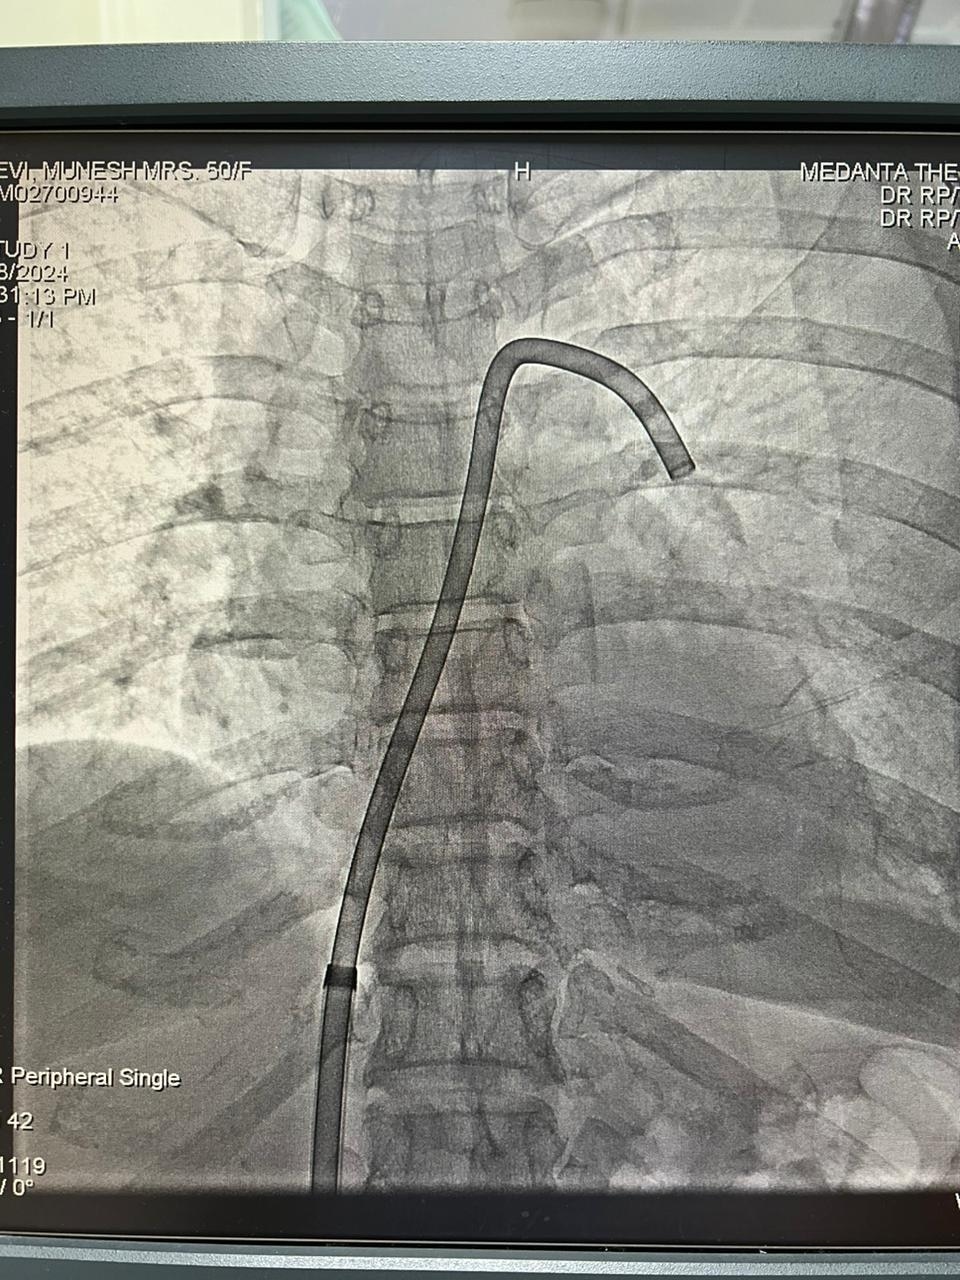

मेदांता के चेयरमैन डॉ. नरेश त्रेहान ने बताया कि सर्जरी में छाती और धमनियों को खोलने के बजाए खून के थक्कों को Suck Out कर बाहर निकाल सकते हैं. एआई की मदद से खून में जमे क्लॉट को पकड़कर बाहर निकाला जा सकता है. हमने पूर्व में भी इसी तरह के बड़े ऑपरेशन किए हैं और उनमें जोखिम भी रहा है.

एआई की मदद से इस ऑपरेशन को करने वाले डॉ. तरुण ग्रोवर बताते हैं कि जब मरीज इमरजेंसी रूम में आए, वे सही तरह से सांस नहीं ले पा रहे थे. उनके पैर में दर्द हो रहा था और उसमें सूजन थी. हमने इस तकनीक की मदद से ब्लड क्लॉट को हटाया. इससे मरीज को तुरंत आराम मिला और उनकी सूजन भी कम हुई. मरीज को 48 घंटे के भीतर डिस्चार्ज भी कर दिया गया.